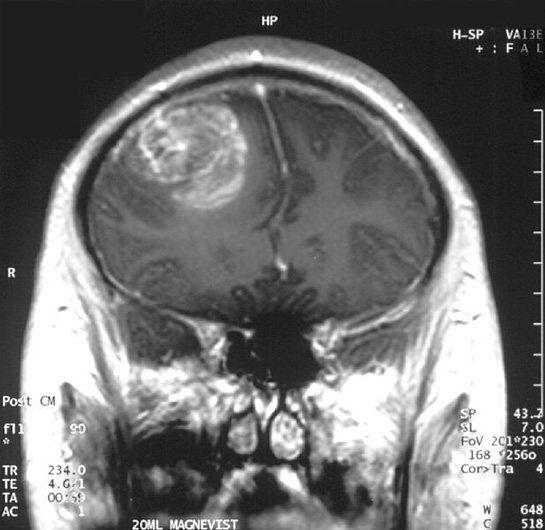

Beyin tümörleri, beyin dokusunda oluşan anormal hücre büyümeleri olarak tanımlanabilir. Bu tümörler, iyi huylu (benign) veya kötü huylu (malign) olabilir. Beyin tümörleri, primer (beyinde başlayan) veya sekonder (başka bir organ veya dokudan yayılan) olarak iki ana kategoriye ayrılabilir. Bu makalede, beyin tümörü çeşitleri ve özellikleri detaylı bir şekilde incelenecektir.

• Glioblastom: En yaygın ve en agresif beyin tümörü türüdür. Genellikle hızlı büyür ve tedavi edilmesi zordur.

• Meningiom: Beynin zarlarında (meninks) gelişir ve genelde iyi huyludur, ancak büyüdüğünde beyin dokusuna baskı yapabilir.